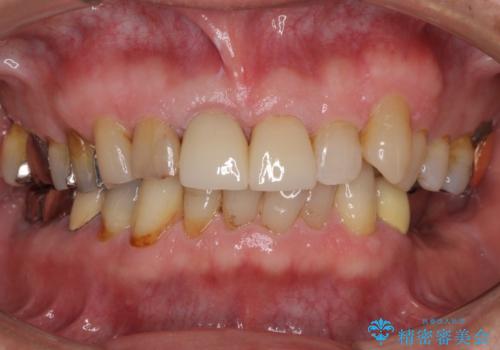

- 前歯がぐらつくことを主訴にご来院された患者様です。ご本人は抜歯と考えており、インプラント以外の治療をご希望でした。しかしながらぐらついていた原因は、古い差し歯が取れかけていたことでした。

遠方から通院されること、仕事上短期間で治療したいとのことを考慮して、残っている歯はかなり小さいものの、保存すべきと判断して当日処置から行いました。

西日本から新幹線でご来院された患者様です。前歯は都内の医院でやりたいとのことで、はるばる通院してくださいました。通院回数が最小限になるよう工夫しました(1回あたりの時間は長くなります)。

残っている歯が小さいと、差し歯はぐらつきやすくなりますが、その形態によっては抜歯を回避できることがあります。